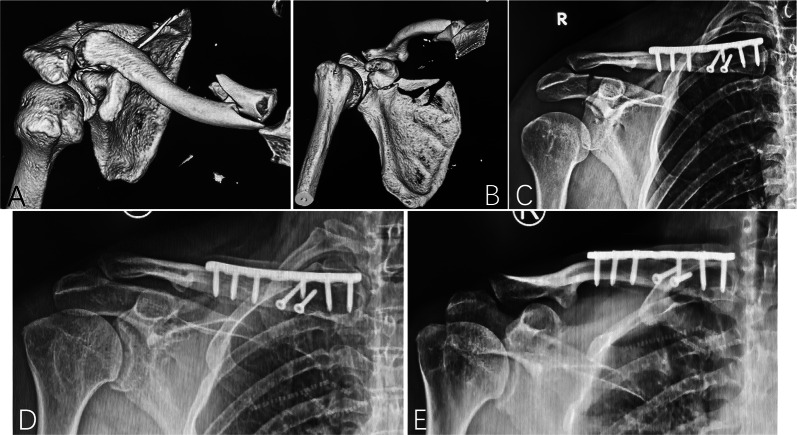

Results: From October 2012 to February 2023, 40 patients were diagnosed with ipsilateral fractures of the clavicle and coracoid process of the scapula, accounting for 1.4% (40/2877) of all clavicle fractures and 5.2% (40/786) of all scapular fractures. This study included 27 patients with follow-up exceeding 12 months: 6 had medial-third clavicle fractures, 12 had middle-third fractures, and 9 had distal-third fractures. According to Eyres' classification, the coracoid fractures included two type I, five type II, eight type III, seven type IV, and five type V fractures. Twenty-two patients received operative treatment, with clavicle fractures fixed with internal plating and 11 coracoid fractures with internal fixation. Bone union was achieved in all patients. The mean Constant-Murley score was 91.2 ± 9.4 and the mean DASH score was 6.4 ± 7.6. Five patients reported mild shoulder pain and five patients developed complications.

Conclusions: Ipsilateral concomitant fractures of the clavicle and coracoid process can occur at various clavicle locations, with shaft and medial fractures more common than previously thought. Displaced fractures can be effectively managed with operative treatment, and coracoid process fixation may not be necessary if satisfactory indirect reduction is achieved after clavicle fixation.